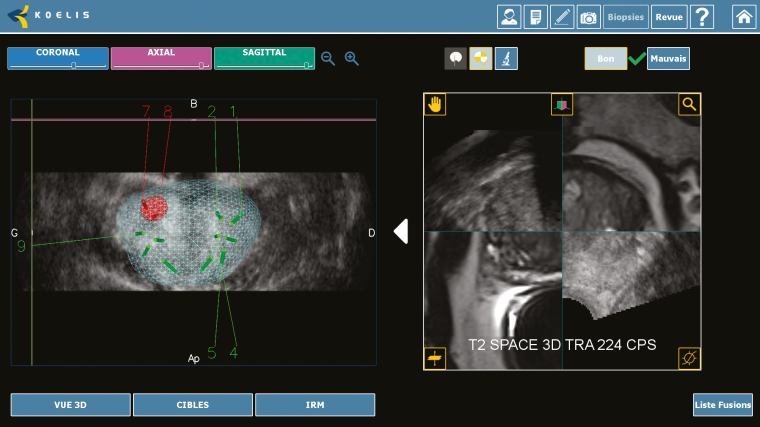

Welche Möglichkeiten eine elastische MRT-3D-TRUS Fusion mit dem Samsung-Ultraschallsystem H60 und der Urostation im praktischen Einsatz bietet, erläutert Priv.-Doz. Dr. Lars Budäus vom Prostatakrebszentrum der Martini-Klinik und des Universitätsklinikums Hamburg-Eppendorf.

Priv.-Doz. Dr. Lars Budäus: Die Martini-Klinik hat sich nach der Gründung durch Prof. Dr. Hartwig Huland rein auf die Behandlung des Prostatakrebses spezialisiert. Die offene und roboterassistierte operative Entfernung der Prostata wird über 2.300 Mal pro Jahr von einem Team von zwölf Ärzten durchgeführt. Darüber hinaus werden gemeinsam mit der Abteilung für Strahlentherapie des UKE alle gängigen Strahlentherapien wie z. B. die perkutane Bestrahlung sowie HDR- und LDR-Brachytherapie eingesetzt. Eine weitere Therapieform – insbesondere für ausgewählte Patienten mit einer niedrigen Risikokonstellation – stellen moderne fokale Therapiemethoden dar, die u. a. den Einsatz der Magnetresonanztomografie (MRT) erfordern. Die MRT wird durch einen sehr erfahrenen Uroradiologen aus der Radiologie des UKE durchgeführt. Hochwertige MRT-Untersuchungen spielen auch eine entscheidende Rolle bei der MRT-3D TRUS Ultraschallfusionsbiopsie der Prostata mit der H60 und Urostation.

Dr. Lars Budäus: Gerade in der Re-Biopsie nach unauffälliger Erstbiopsie und bei weiter steigendem PSA-Wert hilft die MRT-

Ultraschallfusionsbiopsie häufig, relevante Tumoren in atypischen Lokalisationen außerhalb der Areale, die in der randomisierten Biopsie untersucht wurden, zu detektieren. Dies konnte in einer aktuellen Studie zur Auswertung der diagnostischen Wertigkeit des MRTs und der randomisierten zwölffach Biopsie sowie in weiteren umfangreichen multizentrischen Studien gezeigt werden.

Dr. Lars Budäus: Die MRT-3D-TRUS Fusions-biopsie bietet gerade jungen Patienten mit dem klinischen Verdacht auf das Vorliegen eines okkulten, d. h. bisher noch nicht detektierten Tumors durch einen steigenden PSA-Wert und Patienten in der aktiven Überwachung im Rahmen der Re-Biopsie ein höheres Maß an diagnostischer Genauigkeit im Vergleich mit der Standardbiopsie.